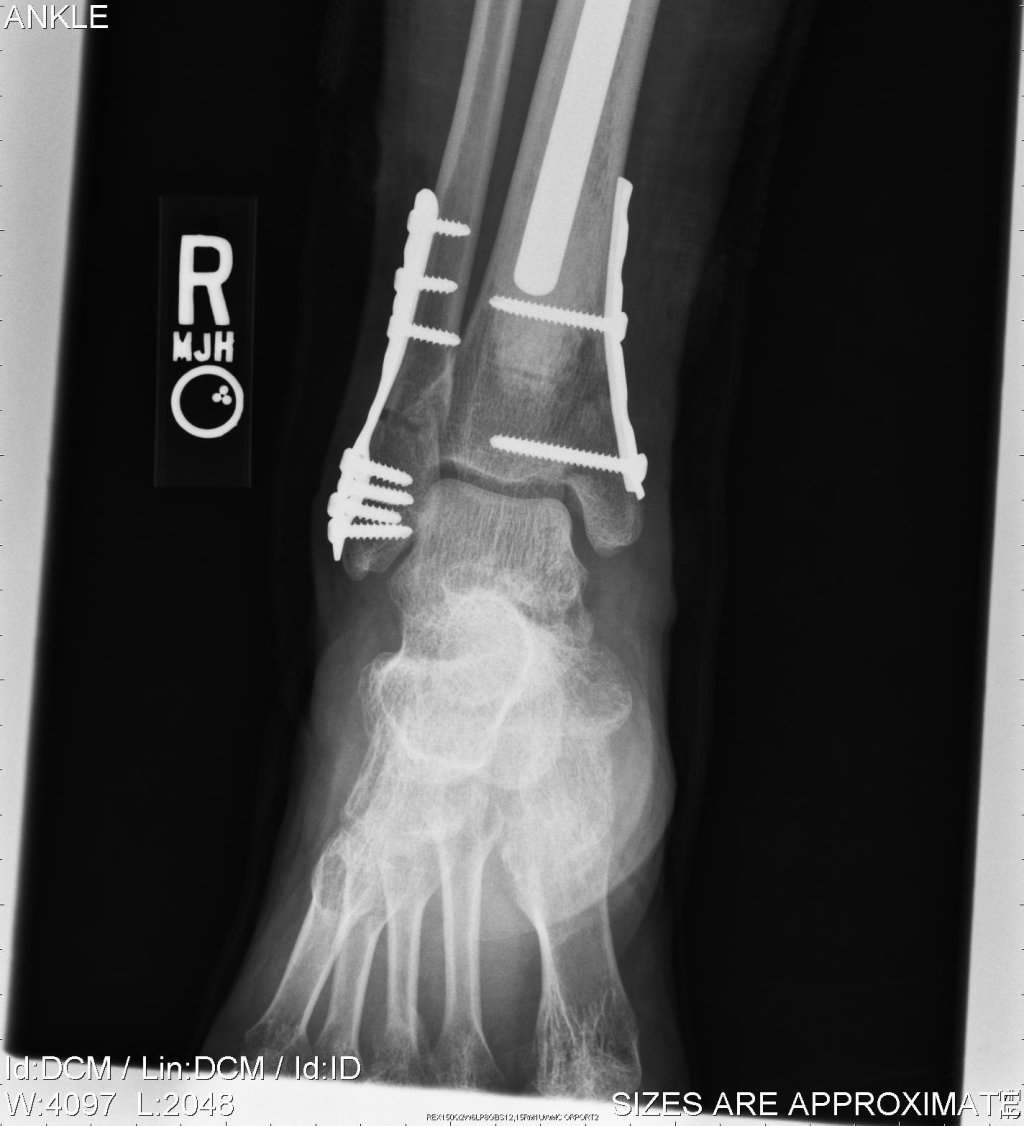

Settimana scorsa un caro amico mi ha fatto “visionare” la radiografia di un suo amico operato dopo una frattura del perone a livello della caviglia,…